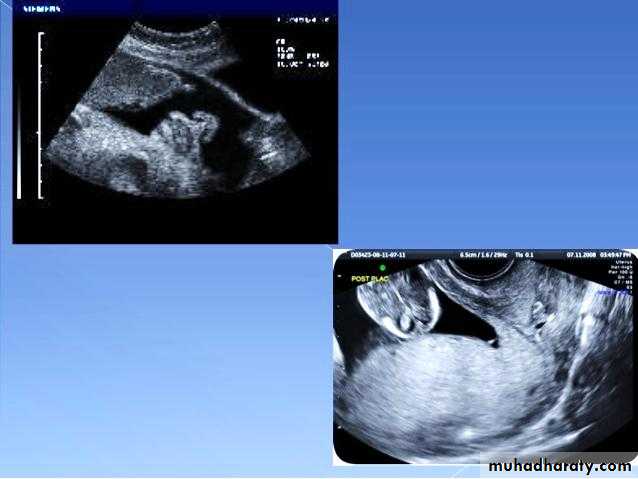

Ectopic pregnancy refers to the implantation of a fertilised ovum outside of the uterine cavity.

Radiographic features

Ultrasound

The ultrasound exam should be performed both transabdominally and transvaginally. The transabdominal component provides a wider overview of the abdomen, whereas a transvaginal scan is important for diagnostic sensitivity.

Positive sonographic findings include:

uterus

empty uterine cavity or no evidence of intrauterine pregnancy

Pseudo gestational sac or decidual cyst: may be seen in 10-20% of ectopic pregnancies

Direct visualization of the sac at the adenxia .